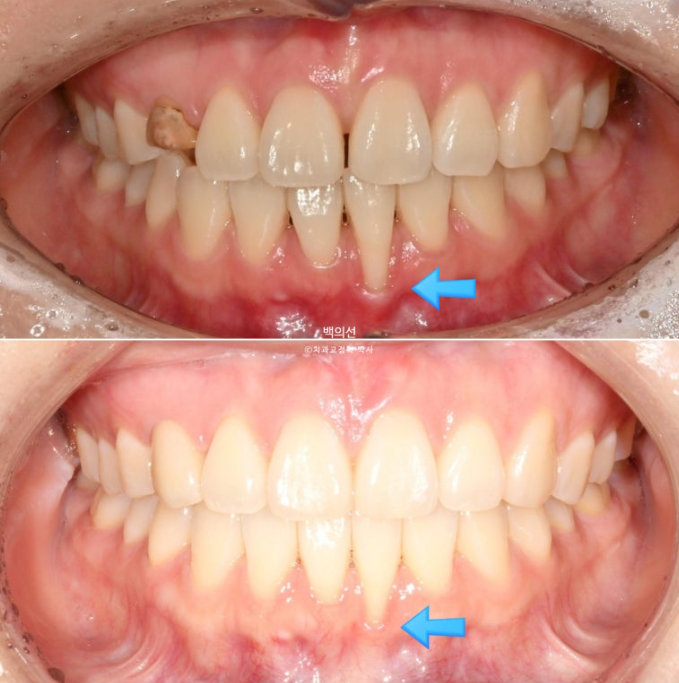

아래 앞니 하나가 뿌리가 바깥으로 나가면서 잇몸퇴축이 심합니다.

잔존유치는 영구치 송곳니가 매복되는 바람에 남아있는 상태입니다.

색이 어두운 치아는 잔존유치에 레진을 덮어놓은 상태이고 이번기회에 재교정을 하면서 이 치아도 변색된 레진을 제거하고 라미네이트든 크라운이든 깔끔하게 치료를 원하셨습니다.

아래 앞니 뿐만 아니라 파란화살표 앞니도 뿌리가 앞으로 나가있습니다. 아직 아래앞니처럼 잇몸퇴축이 일어나지는 않았지만, 튀어나간 뿌리를 입천장쪽으로 데려오는 치료를 해야 잇몸이 내려가는걸 예방할 수 있습니다.

변색된 레진을 제거하고 모습을 드러낸 잔존유치 입니다. 이제 보철 준비를 해야합니다. 안정성을 위해 라미네이트 대신 크라운으로 수복하기로 합니다.

크라운 수복이 끝난 후 어태치먼트를 전부 제거하고 치료를 마쳤습니다.

어떤게 크라운이고 어떤게 자연치 송곳니인지 분간이 잘 되지 않습니다.

주목할만한 점은 바로 치료 후 잇몸퇴축이 완화된 점입니다.

잇몸이 내려간 치아의 튀어나온 뿌리를 안으로 넣어줌으로써, 잇몸이 내려가 뿌리가 노출된 면적이 줄어들었습니다.